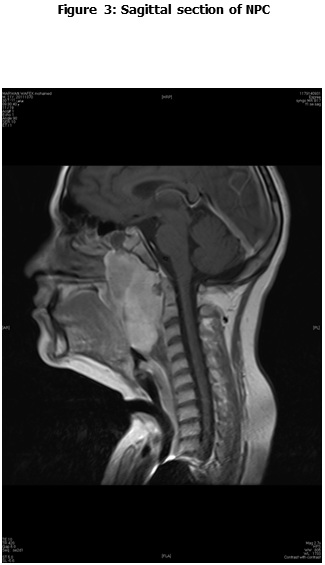

This is a retrospective study including all the newly diagnosed pediatric NPC who were diagnosed and treated at the Children Cancer Hospital Egypt (CCHE) during the period from July 2007 to December 2012. All imaging studies (e.g., CT or MRI scans) were reviewed by a senior head and neck radiologist for proper staging and assessment of tumor response. Patients were staged according to AJCC staging system. Modified version of the Response Evaluation Criteria in Solid Tumor (RECIST) was used to assess response.

This is a retrospective study including all newly diagnosed pediatric NPC at Children Cancer Hospital Egypt CCHE during the time period from July 2007 to December 2012. The patients' profiles were systematically reviewed for characteristics including pathology, laboratory, radiological work up and documented toxicities. All imaging studies (e.g., CT and MRI scans) were reviewed by a senior head and neck radiologist for proper staging and assessment of tumor response.

Pretreatment evaluation included a complete history and physical examination, complete blood count, serum biochemistry tests (including evaluation of electrolyte levels, hepatic and renal function tests), CT or MRI scans of the head and neck region, chest and bone scan. During therapy weekly examinations and laboratory evaluations were performed. Tumor response was assessed by clinical examination with appropriate MRI imaging studies after completion of neoadjuvant chemotherapy and at the end of radiotherapy.